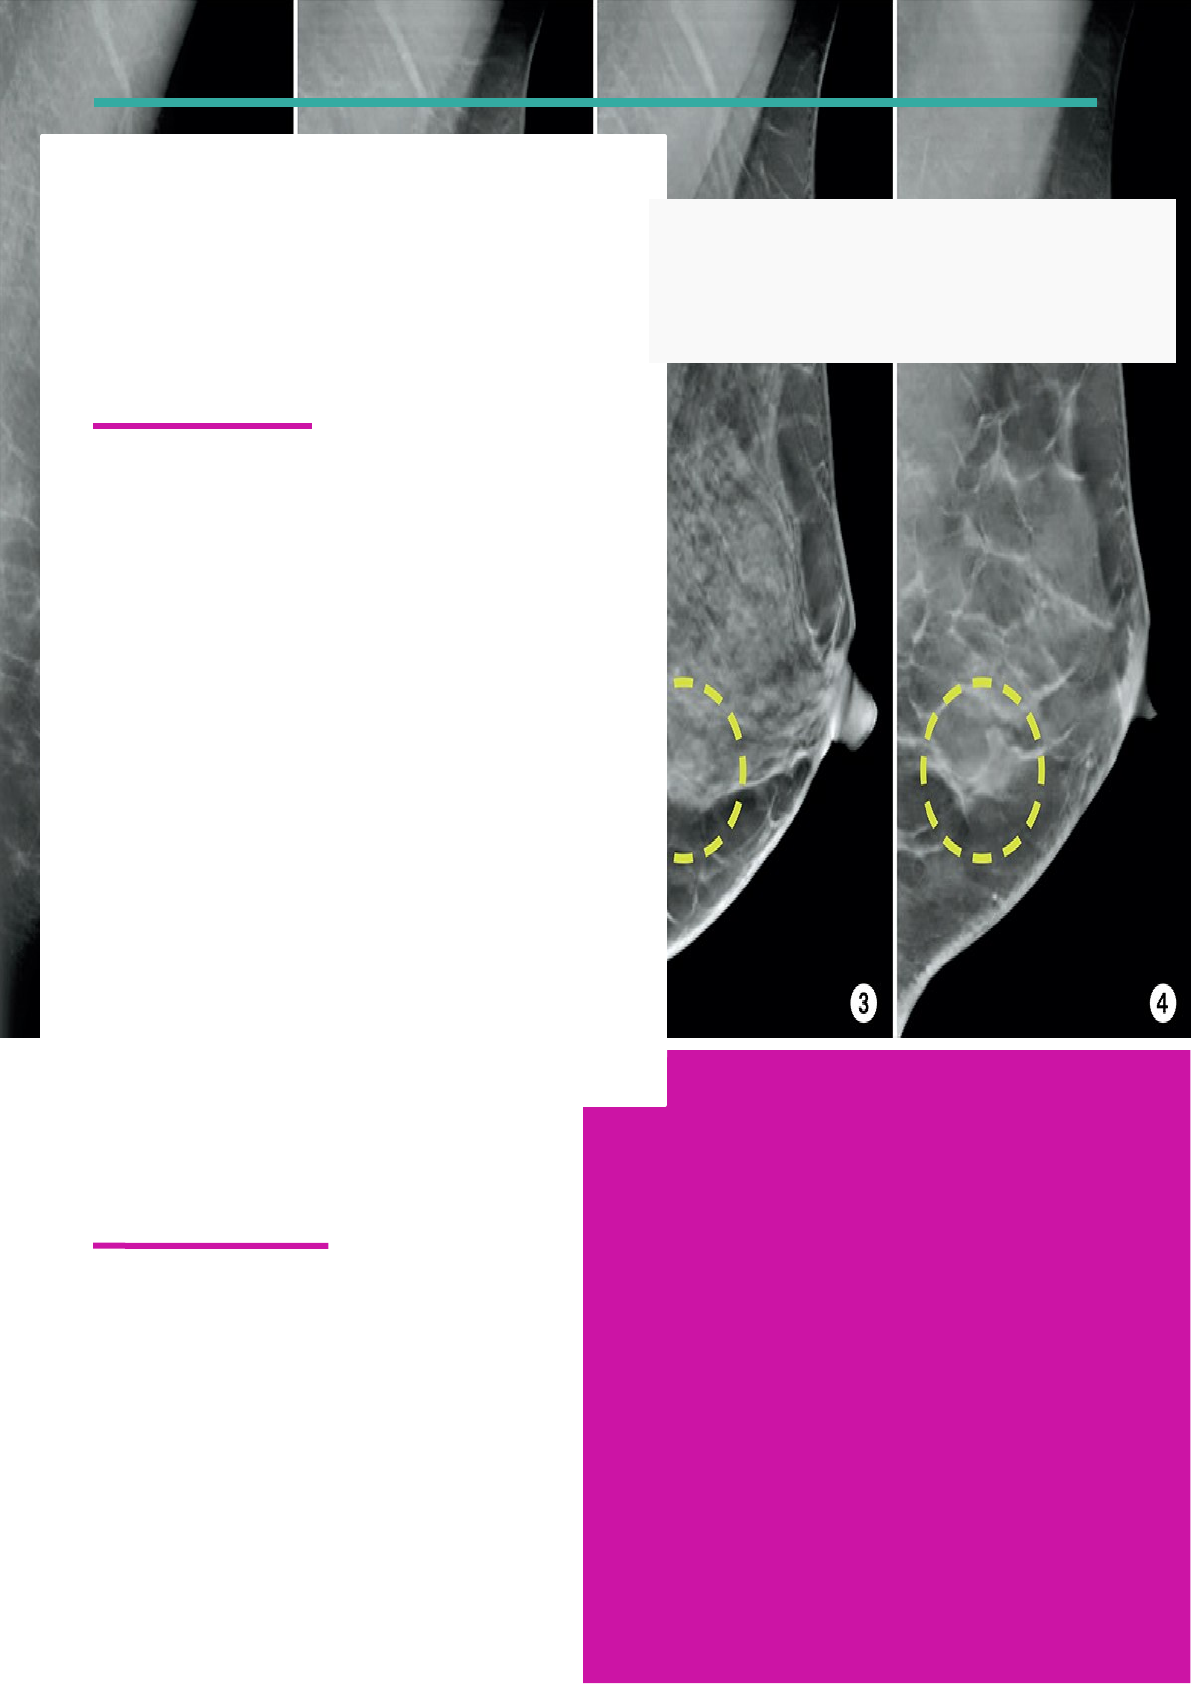

O método de avaliação é o BIRADS, onde o palestrante deu uma breve explicada, de como é dividido e suas explicações. Vimos que é dividido em níveis do 0 a 6:

0 – Não consegui identificar logo de cara e precisa de um exame complementar como a Ultrassom ou a RM;

1 – Nenhum achado;

2 – Achado benigno;

3- Achado provavelmente benigno;

4- Achado suspeito;

5- Achado altamente suspeito;

6- Lesão Maligna/ Câncer.

Para iniciar o processo de diagnóstico de câncer, há necessidade passar por três etapas que são fundamentais para conclusão do diagnóstico: exames físicos, exames complementares e o exame patológico. Para o exame físico o mais conhecido é a palpação ou a alteração visível na região mamaria, já os exames complementares começam pela mamografia, já que é indispensável a realização desse exame, depois caso haja a necessidade de realizar outro exame pode ser a USG ou a RM, vai depender do que for encontrado na mamografia. No exame patológico é onde ocorre a biopsia, que pode ser por agulha fina, agulha grossa ou a momotomia.